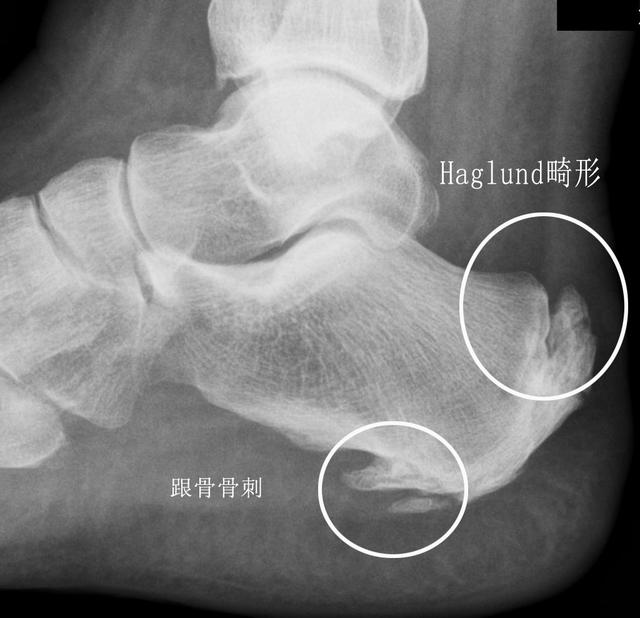

Haglund综合征诱发的跟骨痛

这种疾病其实并不少见,只是很多时候并没有被诊断出来,只是当做了普通的跟腱炎去治疗了。下面这个患者就是谢医生在门诊发现的一例这种疾病的患者照片,看过之后大家就会对这种疾病有一个比较深的认识。

这个疾病有三个特点,就是跟腱止点处的无菌性炎症、骨性增生肥大以及皮下或跟腱下滑囊炎,这其中以骨性的增生肥大最为显著。在这个疾病的早期,骨质增生并不影响生活的时候,我们采取保守治疗的办法。当发展到晚期需要的治疗和其他的跟痛疾病不同,我们建议手术治疗,切除增生的骨赘,重建跟腱